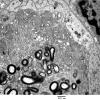

PERIPHERAL NEUROPATHY

4 AXONAL DEGENERATION

3 Electron Microscopy (3)